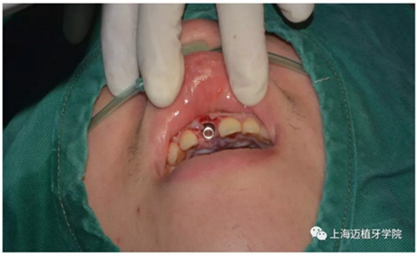

拔除殘根切開(kāi)翻瓣

植入植體DTS:4.1*10 15A042/0061